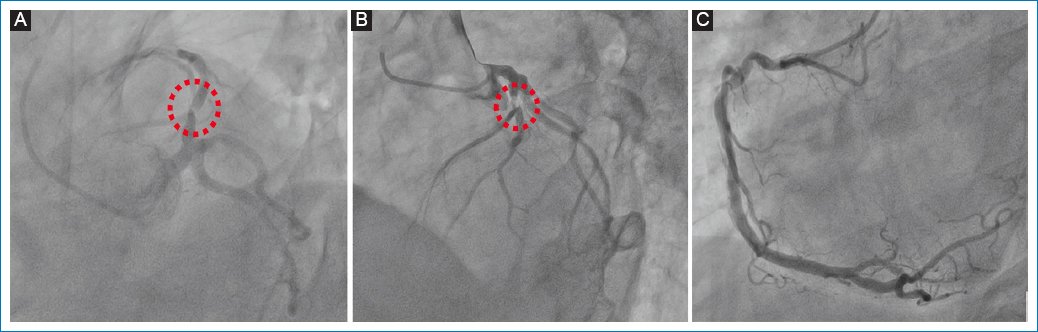

CS was treated pharmacologically with dual antiplatelets, atorvastatin, and noradrenaline paired with levosimendan (intravenous [IV] continuous infusion of 0.2 μg/kg/min for 24 h). A coronary angiography was immediately performed, revealing left anterior descending artery (LAD) lesions, and stents were implanted successfully (Fig. 4).

Figure 4. Coronary angiography. A and B: involvement of the left anterior descending artery (red dotted line); C: right coronary artery without obstructive lesions.